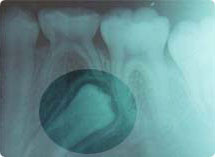

HOME < ¼ºÇü±³Á¤ < °á¼Õ, ¸Åº¹, °úÀ× ¹× ±âÇüÄ¡